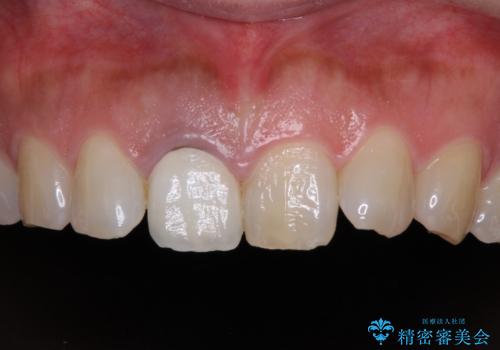

- セラミッククラウンが白すぎる前歯と、放置している奥歯を気にして来院された患者様です。

前歯のセラミッククラウンは将来ホワイトニングをするつもりで白くしたものの、それほど白くならず、ホワイトニングも面倒くさいとのことで白すぎる印象となっていました。

前歯のセラミッククラウンは周りの歯と調和させるためにオーダーメイドタイプのものをおすすめしましたが、元が白すぎていたため、概ね色合いが合えば大丈夫であるとのことで、既製パターンの色調で仕上げました。